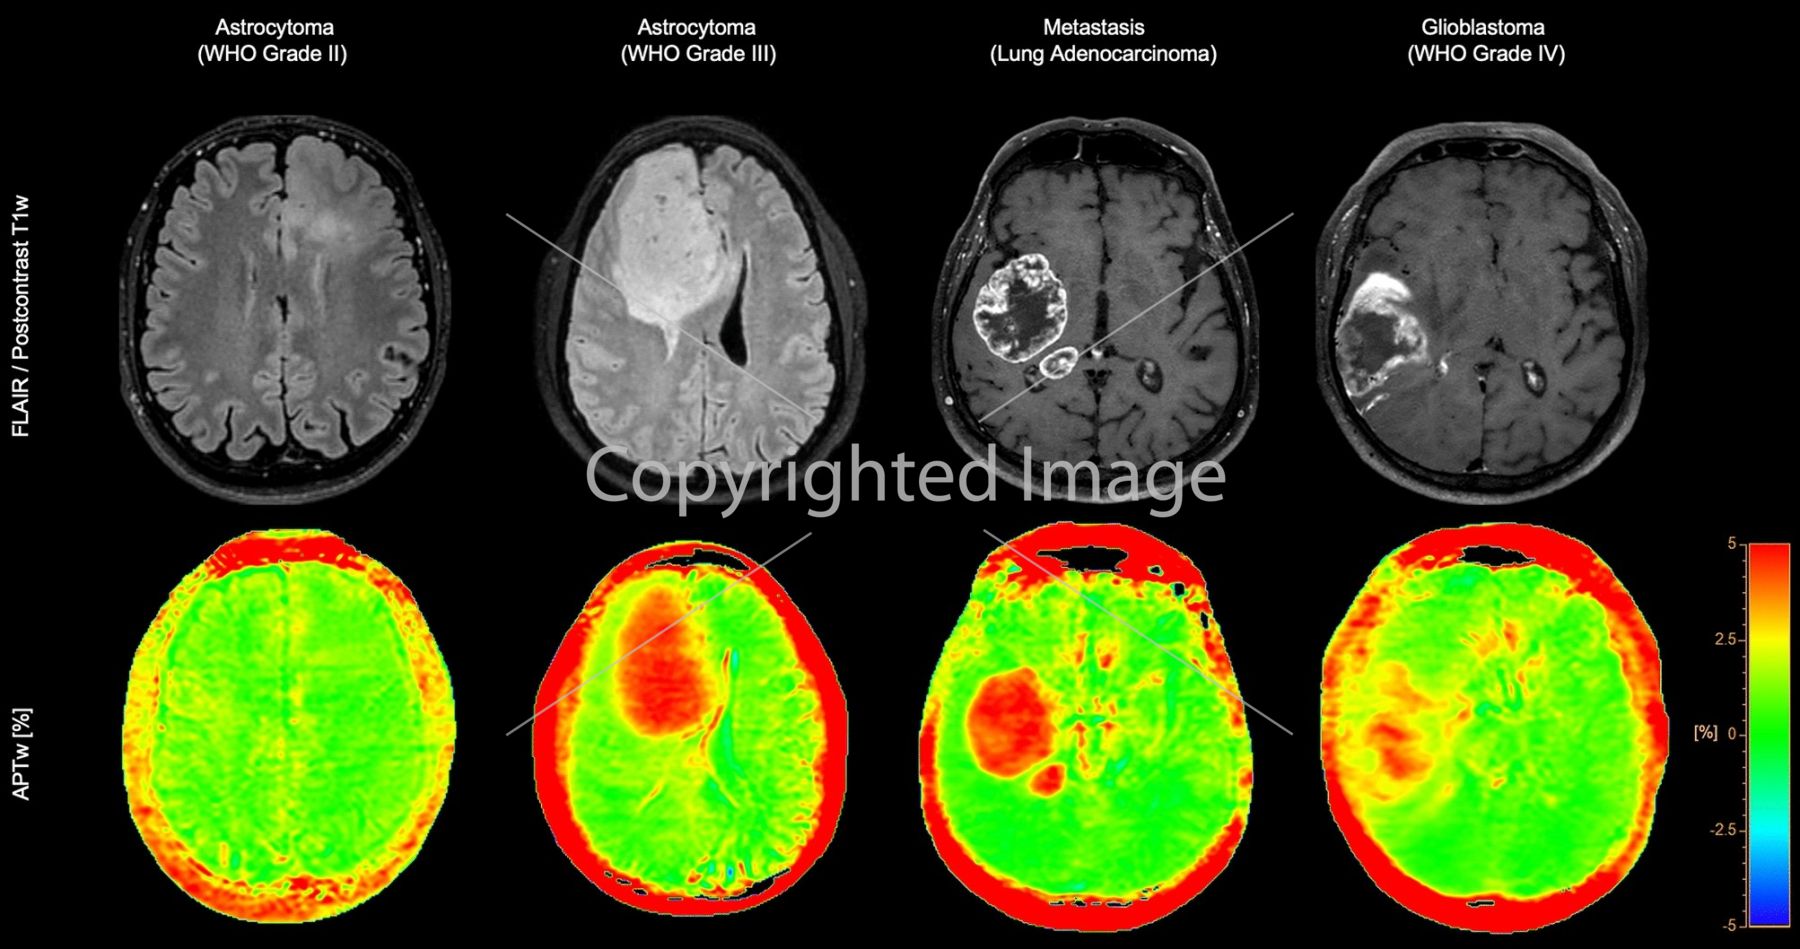

Діагностична впевненість у нейроонкології

3D APT (Amide Proton Transfer) – унікальний метод МРТ-візуалізації головного мозку без використання контрасту.

Він використовує наявність ендогенних клітинних білків для створення МР-сигналу, що безпосередньо корелює з проліферацією клітин – важливим індикатором пухлинної активності.

3D APT підвищує діагностичну впевненість при нейроонкологічних дослідженнях.